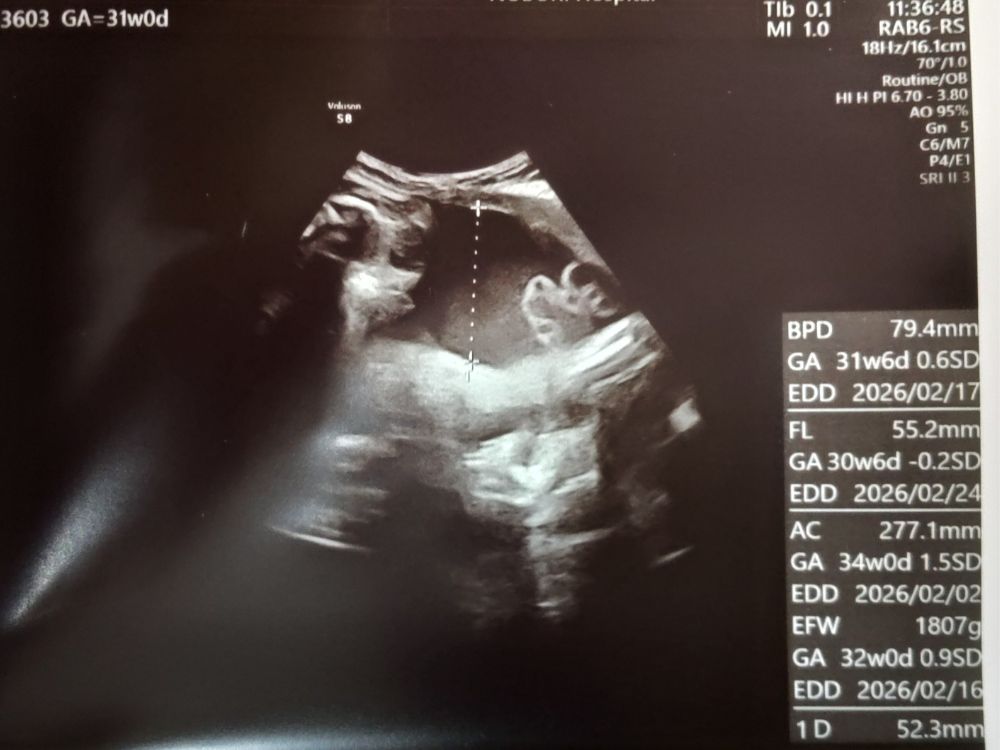

- 胎児体重は1,807g

3週間前、28週の健診では1,200g弱だったので、

500g以上も増えていてびっくり!